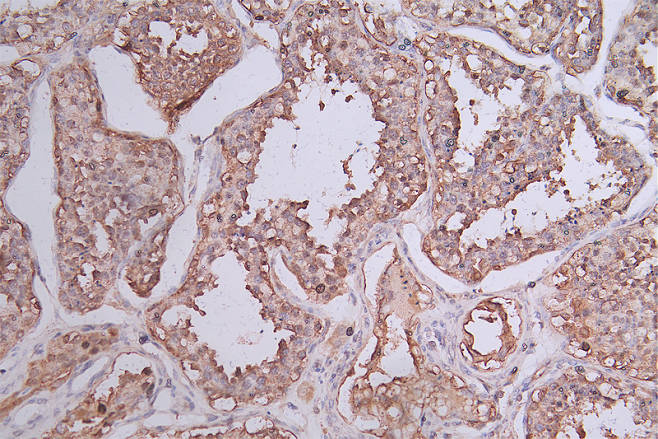

IHC image of CSB-RA644510A0HU diluted at 1:50 and staining in paraffin-embedded human testis tissue performed on a Leica BondTM system. After dewaxing and hydration, antigen retrieval was mediated by high pressure in a citrate buffer (pH 6.0). Section was blocked with 10% normal goat serum 30min at RT. Then primary antibody (1% BSA) was incubated at 4°C overnight. The primary is detected by a Goat anti-rabbit polymer IgG labeled by HRP and visualized using 0.74% DAB.

IHC image of CSB-RA644510A0HU diluted at 1:50 and staining in paraffin-embedded human rectal cancer performed on a Leica BondTM system. After dewaxing and hydration, antigen retrieval was mediated by high pressure in a citrate buffer (pH 6.0). Section was blocked with 10% normal goat serum 30min at RT. Then primary antibody (1% BSA) was incubated at 4°C overnight. The primary is detected by a Goat anti-rabbit polymer IgG labeled by HRP and visualized using 0.74% DAB.